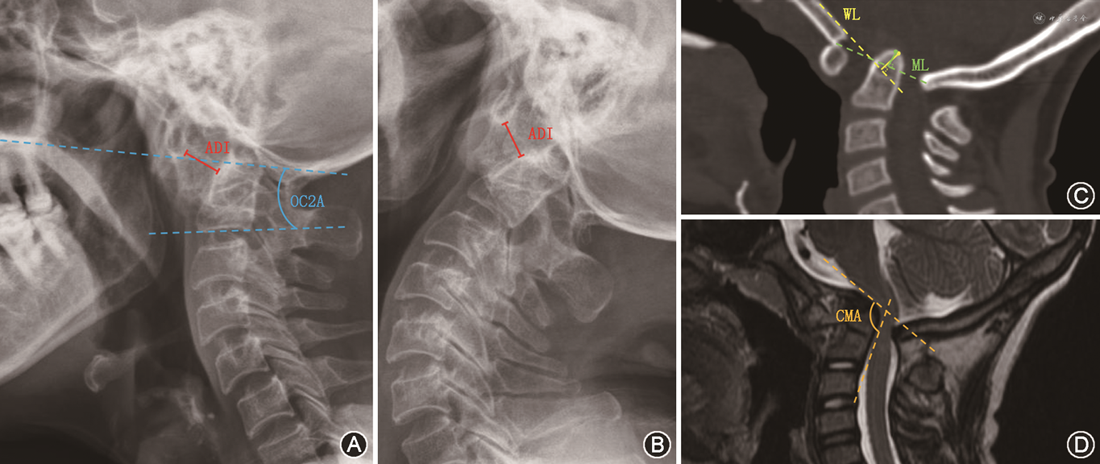

一般指标:包括年龄、性别、手术时间、出血量、住院及随访时间等。神经功能:于术前及末次随访时根据日本骨科学会(Japanese Orthopedic Association,JOA)评分标准(17分法)评价神经功能。影像学指标:分别基于术前、术后颈椎X线片及三维重建CT测量寰齿间距(atlantodens interval,ADI)评估横向脱位;测量齿状突尖至McRae线(McRae line,ML)、Wackenheim线(Wackenheim line,WL)的距离评估纵向脱位,位于参考线上记录为“+”值,线下记录为“-”值(图2)。根据上述距离分别计算术后ADI、ML及WL的复位率=[(术前距离-术后距离)/(术前距离-正常距离)×100%],若术后影像学指标低于或等于临界值则视为完全复位。ADI、ML及WL临界值分别为3、0、0 mm。于颈椎中立位X线片上测量硬腭后上缘与枕鳞皮质外缘最低点的连线与颈2或颈3椎(若存在C2、C3分节不全)下终板线的夹角作为枕颈角(occipitocervical angle,OC2A),若前凸为“+”值,后凸则计为“-”值。基于颈椎平扫MRI测量颈延髓角(cervicomedullary angle,CMA)评估延脊髓受压程度。对于术中行枕骨大孔切除减压的患者,根据笔者的前期报道[6],基于术前CT矢状面重建图像中硬颚后缘、斜坡下缘及枕骨大孔后缘三点角度关系推测术后枕骨大孔后缘位置以行相应影像学指标测量。若CT图像显示枕骨与颈椎骨结构之间形成连续性骨痂,判断为融合。

患者女,62岁,因颈部疼痛2年,加重伴肢体麻木乏力6个月入院,诊断为:(1)颅底凹陷畸形伴AAD;(2)寰枕融合;(3)C2、C3椎体融合。术前JOA评分10分,ADI:5 mm,ML:4 mm,WL:2 mm,CMA:132°。行TSDR枕颈融合术,术后症状缓解,末次随访时JOA评分为15分,ADI:1 mm,ML:0 mm,WL:-1 mm,CMA:141°(图3)。